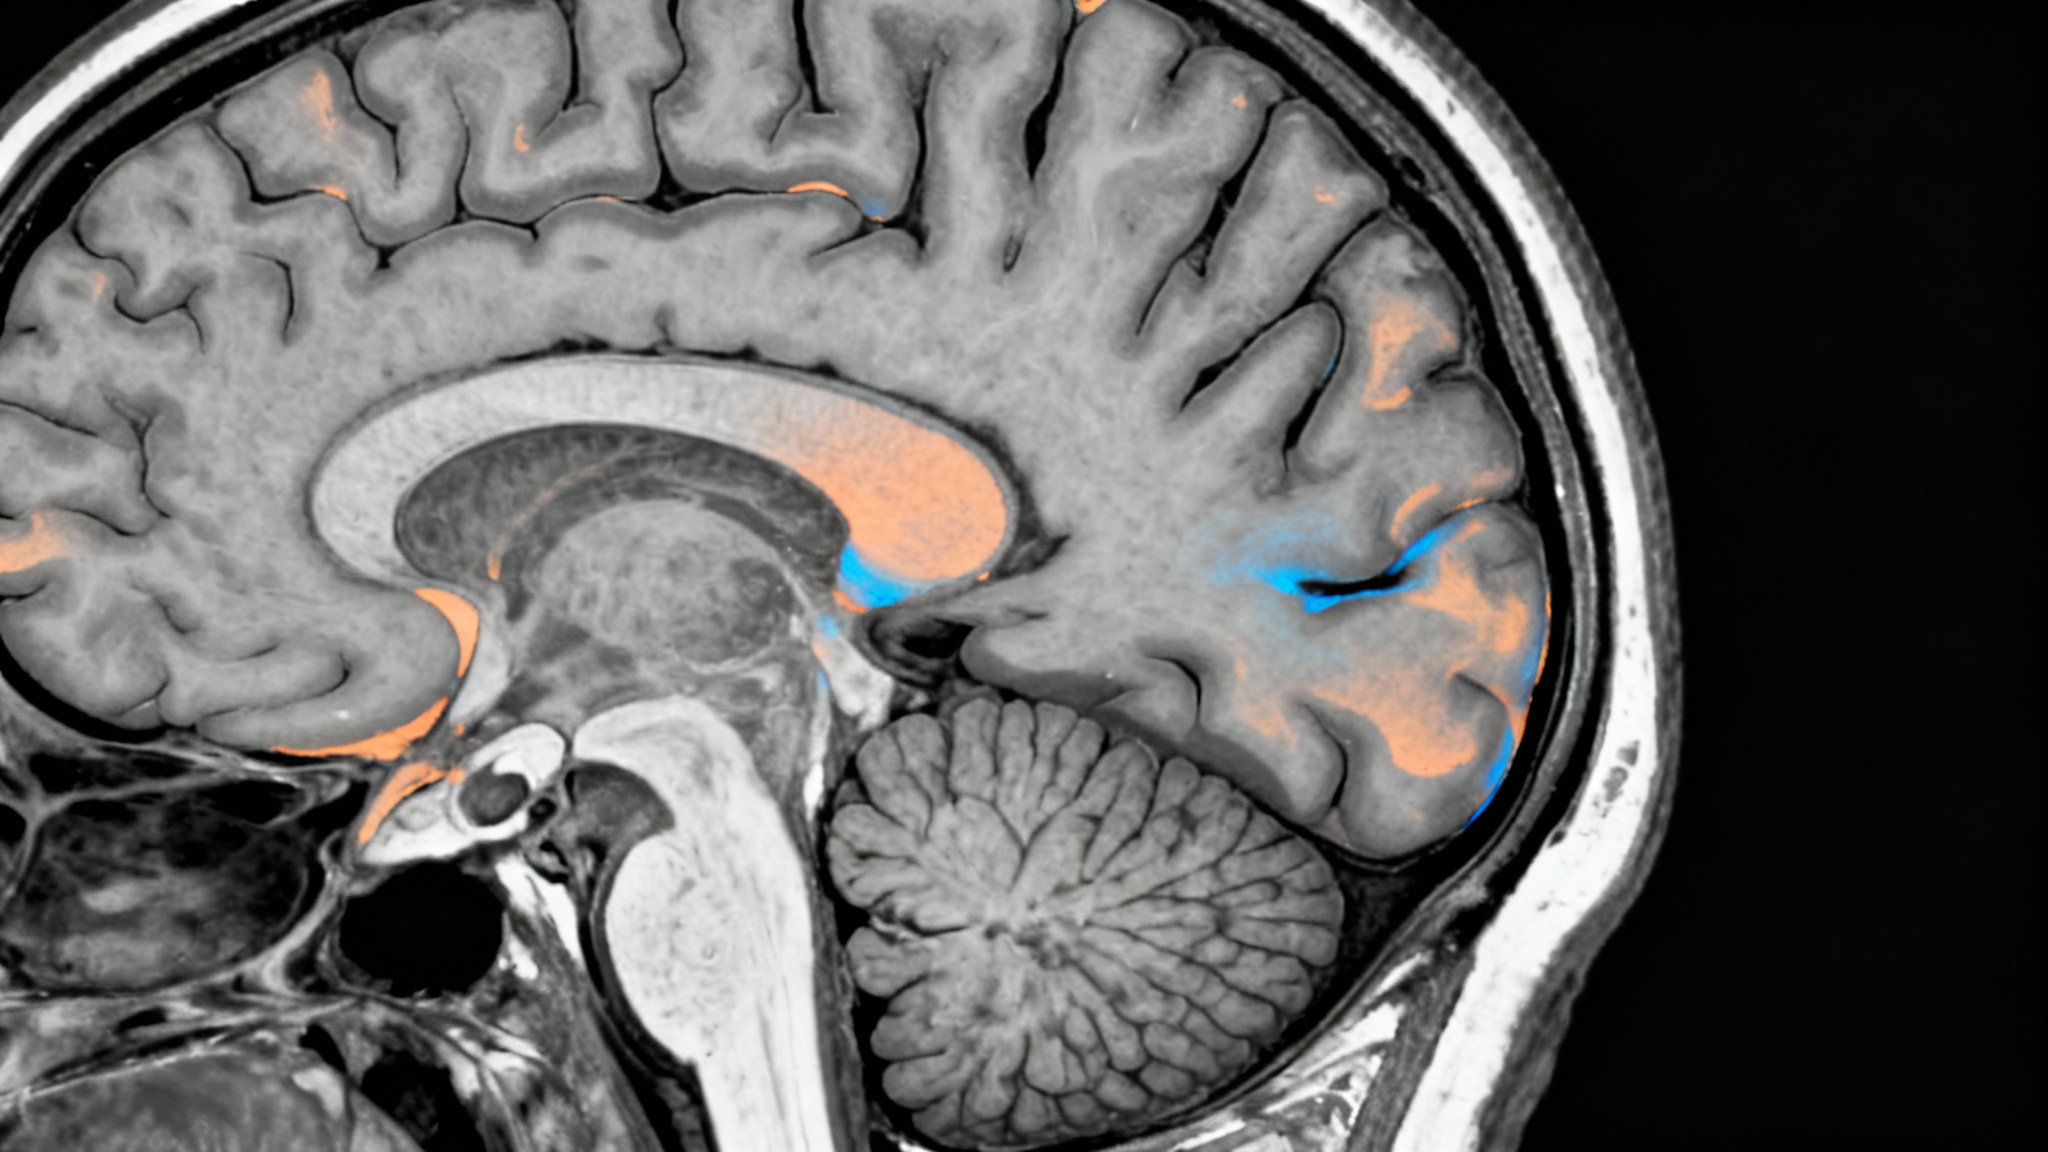

Autorisé par l’Agence Européenne du Médicament (EMA) en avril 2025, le lécanémab représente pourtant une avancée scientifique majeure. C’est la première fois qu’un traitement parvient à cibler directement les plaques amyloïdes, ces agrégats protéiques toxiques dont l’accumulation progressive asphyxie les neurones dans le cerveau des patients.

Mais la prudence des autorités sanitaires repose sur des bases solides. Le lécanémab expose les patients à des risques sérieux. Lors des essais, près de 17 % des sujets ont présenté des anomalies d’imagerie liées à l’amyloïde (ARIA), pouvant se manifester sous forme d’œdèmes cérébraux ou de micro-hémorragies.

Si ces effets secondaires sont la plupart du temps asymptomatiques, 0,3 % des cas se sont révélés sévères, nécessitant hospitalisation et, dans de rares cas, conduisant au décès. Ces contraintes imposent un protocole de suivi par IRM particulièrement strict avant et pendant le traitement, excluant de fait les patients les plus vulnérables. C’est ce coût médical, cette logistique de surveillance intensive, et une efficacité jugée seulement «modeste» qui ont conduit la HAS à estimer que le service médical rendu ne justifiait pas, à ce stade, un remboursement intégral.